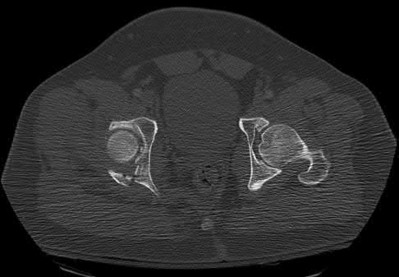

Figure C is an axial CT scan of a lateral compression type 3 (LC3) pelvic ring injury.

Classically, LC3 injuries demonstrate an ipsilateral lateral compression and a contralateral APC (windswept pelvis) fracture pattern. The most common mechanism of injury in these cases is a rollover MVC or pedestrian vs. auto. LC1 injuries are characterized by an oblique or transverse ramus fracture and ipsilateral anterior sacral ala compression fracture, while LC2 injuries consist of a rami fracture and ipsilateral posterior ilium fracture dislocation (crescent fracture). While LC1 injuries can often initially be managed conservatively with protected weight-bearing and close observation, LC2 and LC3 pelvic ring injuries are almost universally operative.

Pennal et al. discuss a radiologic technique for assessing the forces producing pelvic disruption and its use in logically classifying pelvic injury. Based on this radiologic assessment and along with some biomechanical studies, they propose a classification system involving three major forces producing injury that can also be helpful in the management of these patients.

Young et al. performed a retrospective analysis of the plain radiographs of 142 cases of pelvic fractures and identified four patterns of force that presented with distinctive, recognizable radiographic appearances. They describe a classification system for pelvic fractures based on radiographic and clinical findings that correlates with associated injury to soft-tissue structures and enables the surgeon to begin corrective procedures rapidly.

Incorrect Answers:

Answer 1: This represents a lateral compression type 2 injury. Answer 2: This represents a lateral compression type 1 injury.

Answer 4: This represents an anterior posterior compression type 2 injury. Answer 5: This represents an anterior posterior compression type 3 injury.